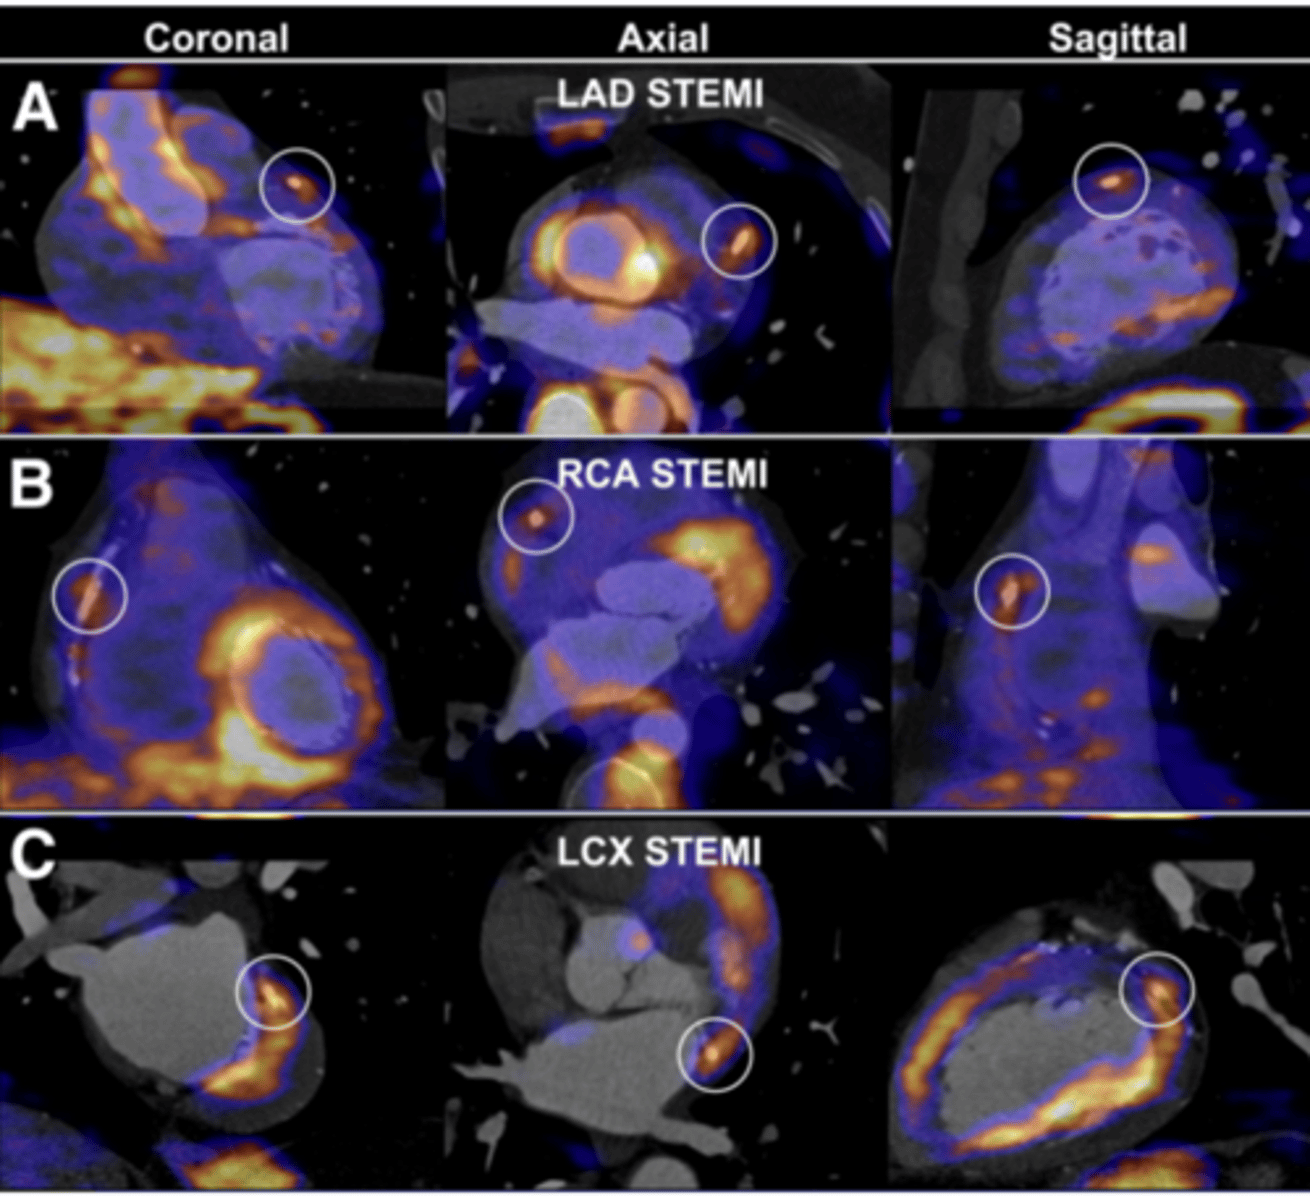

PET scan

Measures important body functions, like blood flow, O2 use, & glucose metabolism

-Used to evaluate tumors & cancers, myocardial function, & brain function

True/false: A PET scan can be used alone or in conjunction with a CT scan.

True